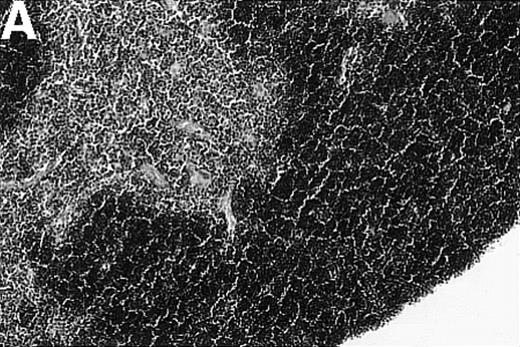

Loss of thymic architecture is a result of acute GVHD but not chronic GVHD

To investigate whether acute or chronic GVHD affects the thymic architecture, an unirradiated P→F1 hybrid model was chosen. After B6→B6D2F1 transplantation, acute GVHD developed, and the thymuses of recipient mice displayed severe morphologic changes (Figure 1). Two weeks after transplantation, the size of the thymus was decreased, and the loss of a regular thymic architecture was apparent with a clear lack of a demarcation between cortex and medulla. In the course of the disease, thymic cellularity progressively decreased and did not recover until the animal's death approximately 4 weeks after transplantation (Figure1D). In contrast, the thymic architecture was not overtly altered during chronic GVHD (DBA/2→B6D2F1). Correspondingly, thymic cellularity was not diminished from this disease when it was analyzed between 1 and 4 weeks after transplantation.

Thymic disease is a consequence of acute but not chronic GVHD.

Acute GVHD was induced by the transfer of 50 × 106parental B6 splenocytes to unirradiated B6D2F1 mice (B), whereas chronic GVHD was induced by the transfer of 80 × 106 parental DBA/2 splenocytes to unirradiated B6D2F1 mice (C). Syngeneically transplanted B6D2F1 mice served as controls (A). Frozen thymic sections (5 μm) were analyzed for histopathology at 2 weeks after transplantation. Magnification ×200. (D) Thymic cellularity as a function of time (total cells per thymus × 10−6) in syngeneically transplanted mice (▵) and in mice with acute (•) and chronic (□) GVHD, respectively. The figure represents combined data (mean ± SEM) of individual mice from at least 8 separate experiments; 20 to 42 mice were analyzed for each group.